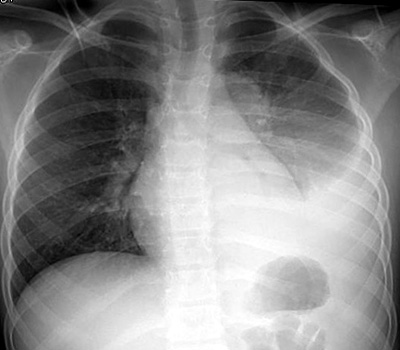

PA and LAT CXR demonstrates a left lower lobe consolidation, representing pneumonia.

Also note the meniscus in the left costophrenic angle indicating a parapneumonic left pleural effusion.